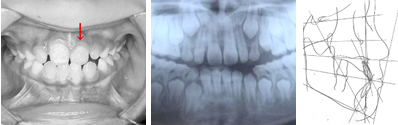

パノラマレントゲンで前歯部分に過剰歯などの異常が無いことを確認。セファログラムレントゲンの分析から、左上の1番目の永久歯(中切歯)が内側に入っていることが問題であることを確認。